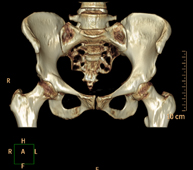

Prueba diagnóstica que consiste en obtener imágenes bi y tridimensionales de la pelvis de alta definición anatómica (estructuras óseas, estructuras vasculares, vejiga, útero y ovarios, próstata y vesículas seminales, uréteres, etc.) mediante el empleo de un equipo de TC (Tomografía Computarizada). La mayoría de estudios requieren el empleo de contraste yodado. - TC Abdominopélvico

Exploración radiológica que mediante un sistema de rayos X y detectores que giran alrededor del paciente, reconstruyendo las imágenes por ordenador (TC Multidetector), permite el estudio de huesos, músculos y articulaciones de la pelvis. - TC de malucs